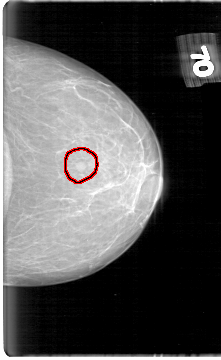

D_4060_1.LEFT_MLO

LEFT_MLO LINES 5326 PIXELS_PER_LINE 3361 BITS_PER_PIXEL 12 RESOLUTION 43.5 OVERLAY

FILE: D_4060_1.LEFT_MLO.OVERLAY

TOTAL_ABNORMALITIES 1

ABNORMALITY 1

LESION_TYPE MASS SHAPE ROUND MARGINS OBSCURED

ASSESSMENT 0

SUBTLETY 4

PATHOLOGY BENIGN

TOTAL_OUTLINES 1

BOUNDARY